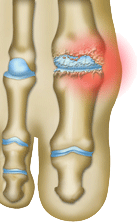

HALLUX RIGIDUS : MECANISME DE LA DEFORMATION

L'HALLUX RIGIDUS est

une arthrose...

...métatarso-phalangienne primitive axée du gros orteil caractérisée par une diminution de la flexion dorsale (hallux rigidus), une prolifération ostéophytique, et une douleur à la mobilisation (hallux dolorosus). Il en résulte une gêne au chaussage par le conflit des ostéophytes avec la tige de la chaussure et des douleurs à la mobilisation, limitant le périmètre de marche.

On explique sa génèse par une notion d’agression microtraumatique et de surcharge mécanique liée à un excès de longueur du gros orteil. Il existe des facteurs constitutionnels expliquant l’HR du sujet jeune, adolescent.